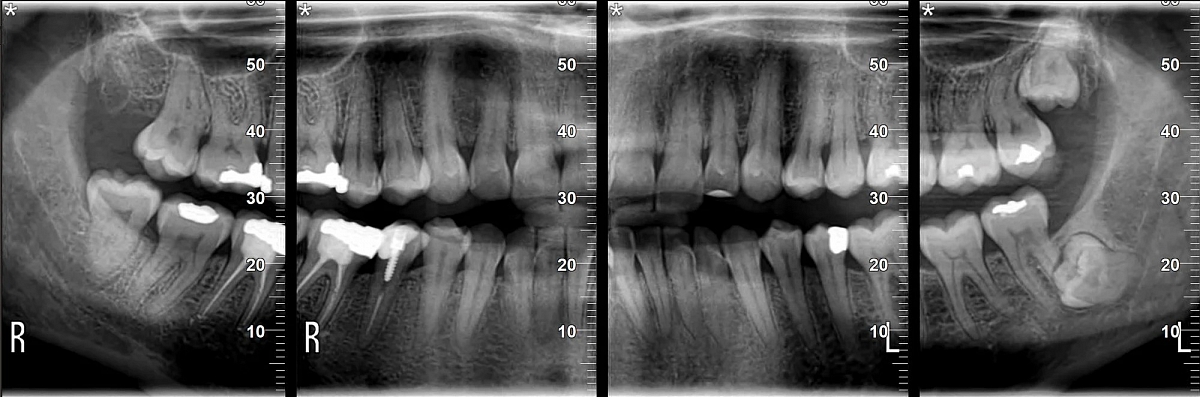

Diagnostinės galimybės

2D vaizdai

- Panoraminiai (PAN) vaizdai su keliais fokusavimo sluoksniais

- Cefalometriniai vaizdai (jei komplektacija su CEPH arm)

- Detalios žandikaulių sričių projekcijos

3D CBCT vaizdai

- SuperHD CBCT su MultiFOV funkcija nuo mažiausio (4x4) iki didžiausio (15x16) lauko

- Greitas 360° skenavimas ir mažos dozės protokolai

- Tiksli kaulinės struktūros diagnostika implantologijai, chirurgijai, ortodontijai ir ENT analizėms

- MultiPAN funkcija – kelios fokusavimo zonos vienu panoraminiu skenu